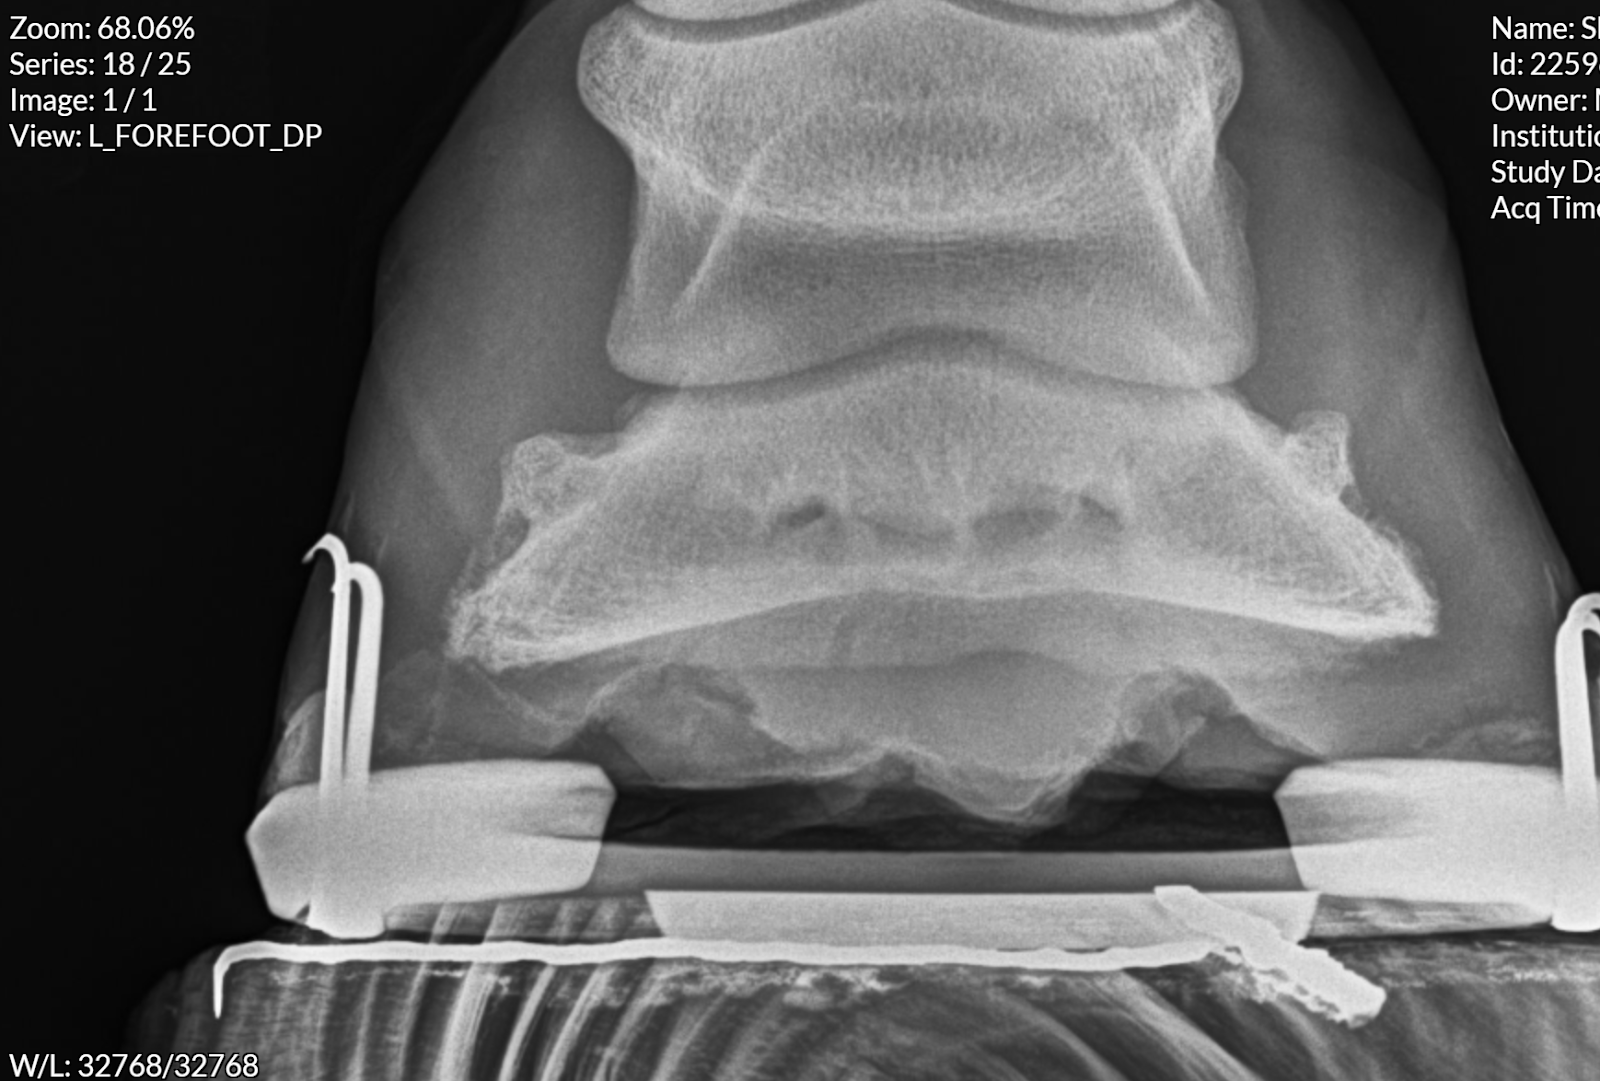

Yoshi makes horse number 3 in just about 6 months that is not sound. It's strange because unlike most of my years of owning Zinger, I actually have disposable income now. Zinger and I strung along while I was in school - I ate about $50/month of groceries so he could have his alfalfa hay. The barn owner let me work off most of my board and even was kind enough to let me increase the work when I could and when I needed to like when my car needed new tires. Yoshi can have whatever he needs that makes him sound. But he still isn't. I realize this is all premature, he may yet be sound when we get his feet straightened out. But there's still some effusion in his front left fetlock that has a little voice going in the back of my head. And I'm not really a voice in the back of my head kinda person, y'know? I'm one of those annoying "If anything can go well, it will" bumper sticker (no I don't actually have one) type of people. I don't tend to worry about things until they're actually a thing. I just have a gut feeling this is not going to turn out well. I'm sure that gut feeling has been shaped by the negative experiences since Zinger's death in 2018, but it still has me considering different... hobbies? lifestyles? life options? I'm not sure what to call horses. Riding is more than a hobby, more than a sport.